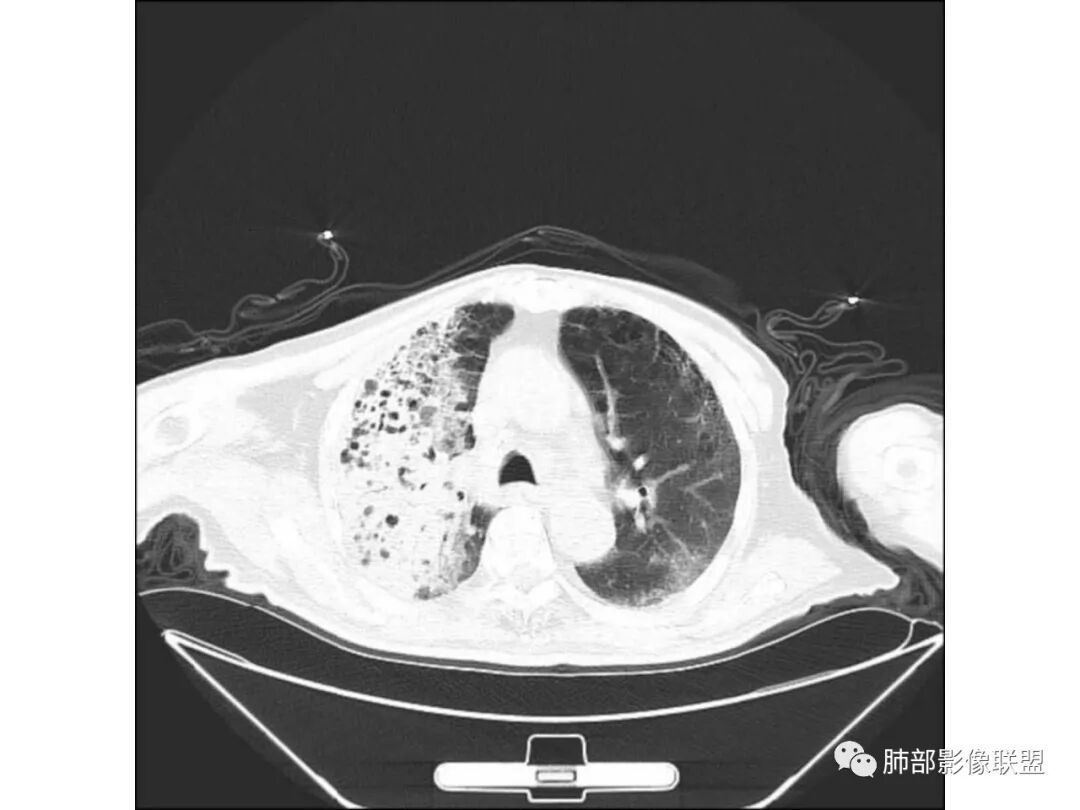

王秀仙:

右肺上叶大片实变,其内可见虫蚀样空洞及扩张支气管,其中一空洞内可见曲菌球样结构,右肺体积略缩小。老年糖尿病患者,慢阻肺背景,考虑右肺上叶干酪性肺炎并曲霉感染。

老年男性,糖尿病患者,右上肺大片实变,内可见多发虫蚀样空洞,右尖段近胸膜处一空洞内可见一类圆形结节影,支气管扩张,淋巴结肿大,双下肺索条,胸膜增厚。结合糖尿病病史,首选考虑结核干酪性肺炎合并曲霉菌感染,待排肺炎型肺癌

老年男性,糖尿病基础,有咳嗽,喘累症状,病程10天,右上肺大片实变,内虫嗜样,无壁空洞,支气管壁增厚,扩张,淋巴结肿大,胸膜增厚,考虑干酪性肺炎,鉴别粘液腺癌。

老年男性,糖尿病病史,慢性病程,右胸廓塌陷,右肺沿支气管分布实变及GGO,叶段分布趋势,其内见支气管充气征及虫蚀样空洞,周围间质受累,指向气道来源病变播散,纵隔淋巴结肿大,密度高伴钙化,综合考虑干酪性肺炎。鉴别肺炎型肺癌。

老年男性,有糖尿病史,右肺上叶大片实变影,有支气管充气征,支气管走行僵直,有扩张,有多发无壁小空洞和俩个稍大空洞,胸膜稍增厚,双下肺野间质性改变,考虑肺结核,干酪性肺炎可能性大。

老年男性,右肺上叶大片实变,边界局部清楚,局部模糊,其内见支气管充气征及多发大小不等的小泡状及分枝状无壁空洞。双肺下叶磨玻璃样间质性改变。综合考虑右肺上叶结核,干酪性肺炎可能。

宇宙星空:

右上肺大片状高密度影,呈蜂窝样改变,部分气腔无壁,部分呈厚壁改变,内部结构紊乱,部分边缘GGO边界清楚,大小不一,病灶近端小远端大,近端支气管壁增厚,支持感染性病变,考虑结核,其内支气管呈枯树枝改变,病灶局部膨隆,内部结构紊乱,边界的GGO部分清楚,恶性(腺癌)待排。